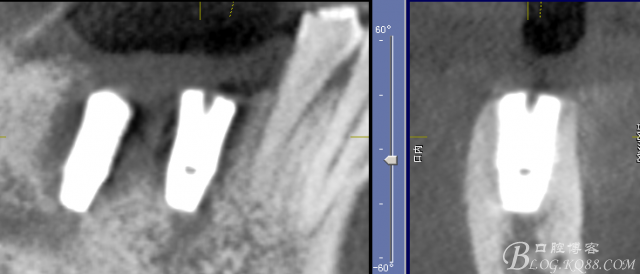

CT可見根管內有白色顯影物和根周較大暗影

三維檢查種植體位置,方向,平行度